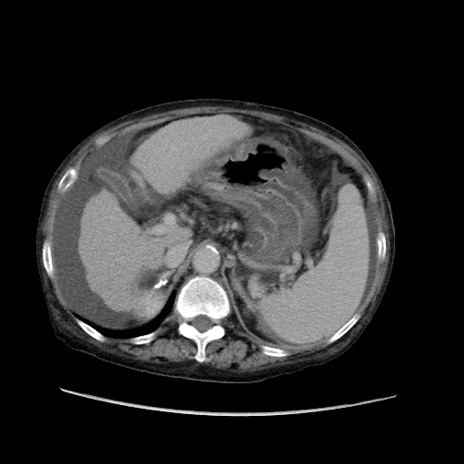

症例31(横断像)

【症例】80歳代 女性

【主訴】腹部膨満感

【現病歴】他院にて肝硬変にてフォロー中。1週間前から便秘、腹部膨満感、臍部腫瘤あり受診となる。

【既往歴】肝硬変

【身体所見】腹部膨隆あり、皮膚変化なし、疼痛なし。

【データ】WBC 4600、CRP 0.25